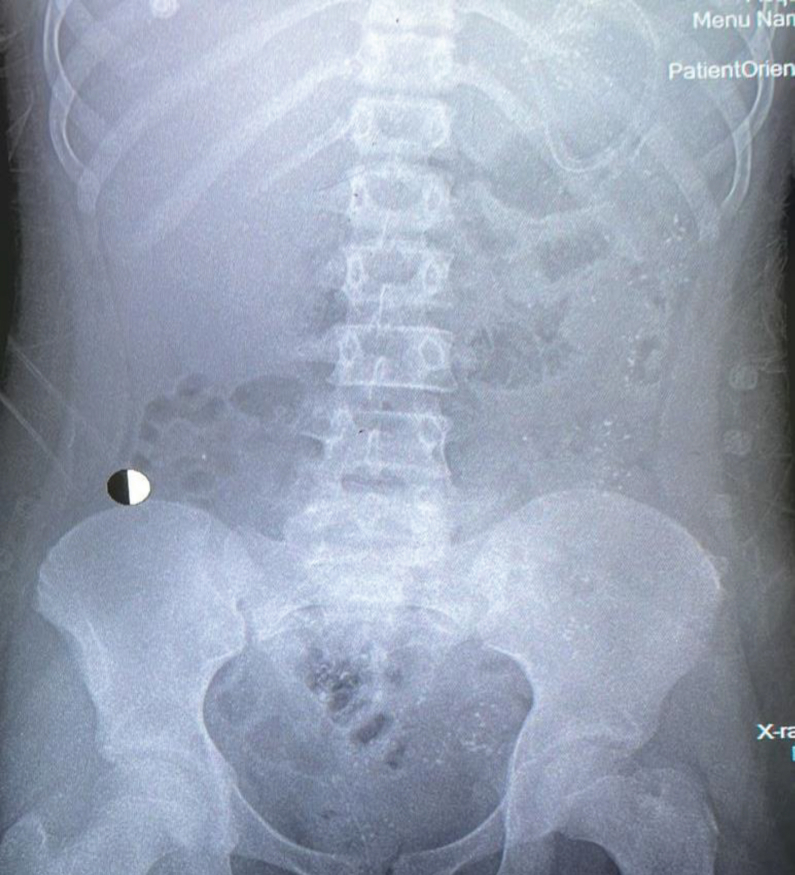

تم توثيق أربع حالات تسمم حادة ناتجة عن تناول شطائر شاورما ملوثة تحتوي على الكاربوفيوران والبيفنثرين، وهي مزيج من الكاربارمات والبيريثرويد على التوالي. الأفراد المتضررون جميعهم أشقاء، وأظهروا درجات متفاوتة من الأعراض السمية، بما في ذلك ارتعاش العضلات، والإفرازات الزائدة، وضيق التنفس. على الرغم من شدة الأعراض، كان لدى ثلاثة من المرضى مستويات طبيعية أو منخفضة طبيعيًا من إنزيم الأسيتيل كولين إستريز، ويرجح أن يكون ذلك بسبب التباين الفردي، أو التأخير في إجراء الفحص، أو سوء التعامل مع العينات. أما المريض الرابع، فقد أظهر نشاطا منخفضا بشكل كبير لإنزيم الأسيتيل كولين إستريز، مما يشير إلى تثبيط شديد، وزادت الحالة تعقيدا بسبب التهاب البنكرياس، مما ساهم في تأخر التعافي. شملت التدخلات العلاجية السريرية المبكرة إعطاء الأتروبين، البراليدوكسيم، ومضاد التسمم الوشيقي بسبب الشك الأولي في وجود تسمم ناتج عن بكتيريا وشيقية. أكدت التحليلات السمومية تسمم الكاربوفيوران.

背景:农药中毒仍然是一个主要的全球健康问题,估计每年造成371,594人死亡。意外和故意接触农药,特别是在发展中国家,都对公共卫生系统构成挑战。在KSA,农药中毒很普遍,而氨基甲酸酯和有机磷等杀虫剂是罪魁祸首。案例介绍:描述了因食用含有呋喃和联苯菊酯(分别是氨基甲酸酯和拟除虫菊酯的混合物)的受污染的沙瓦玛三明治而引起的四个急性中毒病例。受影响的个体,所有的兄弟姐妹,都表现出不同程度的胆碱能症状,包括肌肉抽搐、分泌物过多和呼吸窘迫。尽管症状严重,但3例患者的乙酰胆碱酯酶水平正常或低正常,这可能是由于个体差异、延迟检测或样品处理不当所致。一名患者表现出乙酰胆碱酯酶活性降低,因此表明严重抑制;胰腺炎是导致恢复延迟的另一个并发症。早期临床治疗包括阿托品、普拉多肟和肉毒杆菌抗毒素,因为最初怀疑是肉毒中毒。毒理学分析证实了呋喃中毒,食品安全调查发现在食品加工领域不当使用农药。结论:报告的病例强调了及时毒理学咨询、正确检测和正确的样品处理对农药中毒治疗的重要性。这些调查结果突出表明,必须严格遵守世卫组织的规定,监测农药的使用情况,并采取严格的食品安全措施,以防止今后疫情的爆发。管理这些病例的成功多学科方法表明,临床小组和公共卫生当局之间的协调努力在应对此类公共卫生威胁方面发挥了关键作用。